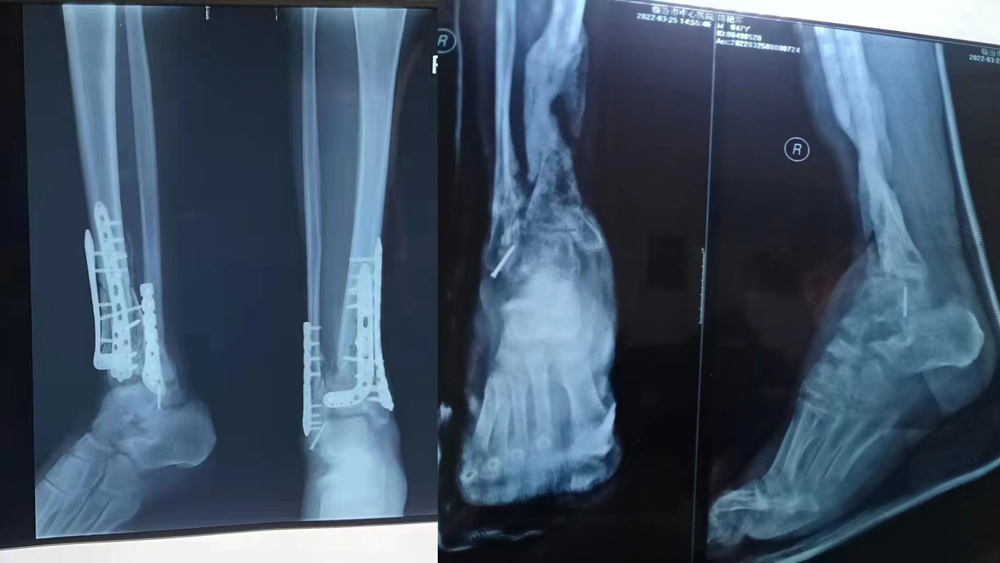

山西省洪洞县患者随先生,2021年2月因车祸造成右小腿胫腓骨开放性粉碎型骨折,在山医xx手术清创整复骨折钢板螺丝钉内固定,术后感染化脓,钢板,骨头外露,左小腿、左脚高度肿胀痛疼,肌腱腐烂、骨头发黑,流污浊脓液,恶臭难闻,其他医院建议截肢,患者及家人又到北京xxx医院、xx医院等均建议截肢…后经人介绍2021年4月来我院,手术取除内固定、取除死骨(右胫骨下段几乎完全取除)、清创病灶,内服、外敷我院研制的系列特效药物等治疗5月余,患者右小腿肿痛消失,伤口愈合痊愈出院,当时告诉患者,因为骨头感染严重,取的骨头太多,需要一年后植骨治疗,没想到患者出院后,坚持服用我院研制的参鹿填髓丸、舒筋接骨丸、海马壮骨胶囊等,患处外敷骨康膏等,骨质破坏修复,骨痂大量生长,已经重新站立起来了,可以自由行走了!